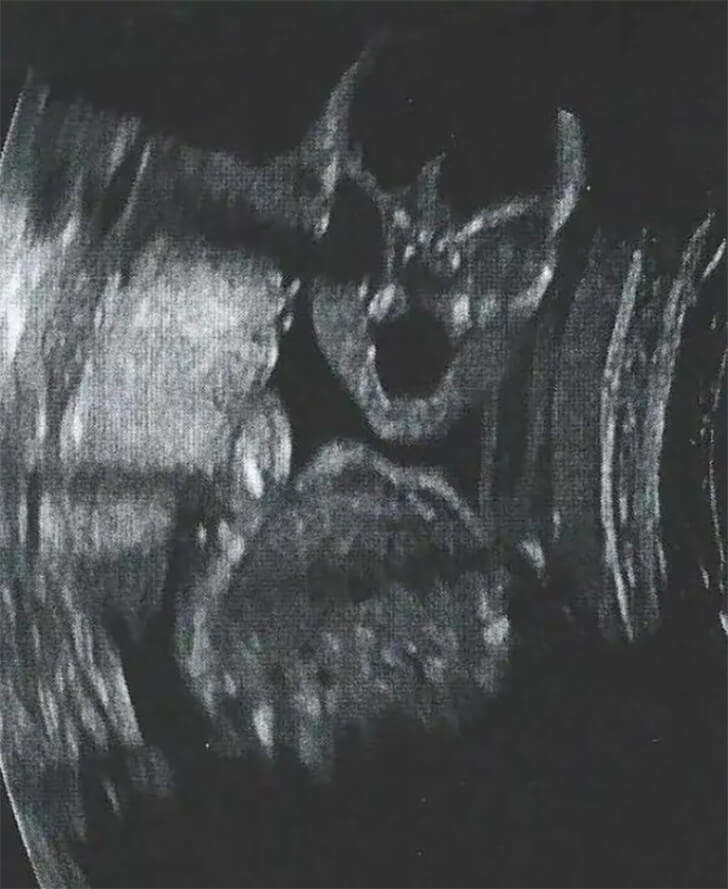

Within the eerie contours of an ultrasound image, an unsettling sight unfolds. The frontal view of a fetus, bathed in the eerie glow of medical technology, takes on a disquieting aspect. Hollow eyes, vacant yet haunting, pierce the viewer’s soul with an enigmatic stare that transcends the boundaries of the womb.

Below, a nose and mouth form an eerie visage, hinting at secrets held within the amniotic shroud. It’s as though this tiny life, still cocooned within its mother’s womb, harbors an ancient knowledge, unsettling in its otherworldly wisdom.